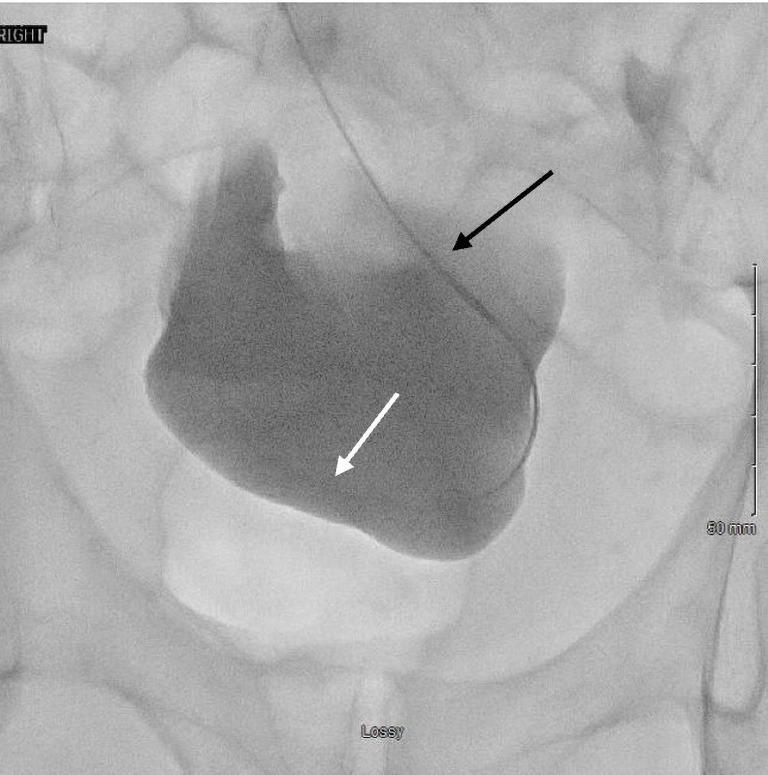

Patients with end-stage renal disease (ESRD) often will ultimately require dialysis to survive. One type of dialysis is peritoneal dialysis (PD), which utilizes the vessel-rich peritoneum as a semi-permeable membrane to filter blood. In order to perform PD, a tunneled catheter must be placed through the abdominal wall and into the peritoneal space, with ideal positioning of the catheter within the most dependent portion of the pelvis, represented by the rectouterine or rectovesical space in women and men, respectively. There are several approaches to PD catheter insertion, including open surgical, laparoscopic surgical, blind percutaneous, and image-guided with the use of fluoroscopy techniques. Interventional radiology (through the use of image-guided percutaneous techniques) is an infrequently utilized resource to place PD catheters, and offers real-time imaging confirmation of catheter positioning with similar outcomes to more invasive surgical catheter insertion approaches. Although the vast majority of dialysis patients receive hemodialysis instead of peritoneal dialysis in the United States, some countries have moved towards a "Peritoneal Dialysis First" initiative, prioritizing initial PD, as it is less burdensome on healthcare facilities as it can be performed at home. In addition, the outbreak of the COVID-19 pandemic has produced shortages of medical supplies and delays in care delivery worldwide, while simultaneously generating a shift away from in-person medical visits and appointments. This shift may be met with more frequent utilization of imaged-guided PD catheter placement, reserving surgical and laparoscopic placement for complex patients who may require omental periprocedural revisions. This literature review outlines a brief history of PD, the various techniques of PD catheter insertion, patient selection criteria, and new COVID-19 considerations, in anticipation for the increased demand for PD in the United States.

终末期肾病(ESRD)患者往往最终需要透析才能存活。一种透析方式是腹膜透析(PD),它利用血管丰富的腹膜作为半透膜来过滤血液。为了进行腹膜透析,必须将一根隧道式导管经腹壁置入腹膜腔,导管的理想位置在骨盆最靠下的部分,在女性为直肠子宫陷凹,在男性为直肠膀胱陷凹。腹膜透析导管插入有几种方法,包括开放手术、腹腔镜手术、盲法经皮插入以及使用荧光透视技术的影像引导插入。介入放射学(通过使用影像引导经皮技术)是一种较少用于放置腹膜透析导管的资源,它能提供导管位置的实时影像确认,其结果与更具侵入性的手术导管插入方法相似。尽管在美国绝大多数透析患者接受的是血液透析而非腹膜透析,但一些国家已转向“优先腹膜透析”倡议,将初始腹膜透析作为优先选择,因为它对医疗机构的负担较小,因为可以在家中进行。此外,新冠疫情的爆发在全球范围内造成了医疗用品短缺和护理交付延迟,同时导致人们减少了面对面的医疗就诊和预约。这种转变可能会使影像引导腹膜透析导管置入的使用更加频繁,而将手术和腹腔镜置入保留给可能需要在围手术期对网膜进行修正的复杂患者。这篇文献综述概述了腹膜透析的简史、腹膜透析导管插入的各种技术、患者选择标准以及新冠疫情的新考量因素,以应对美国对腹膜透析需求的增加。